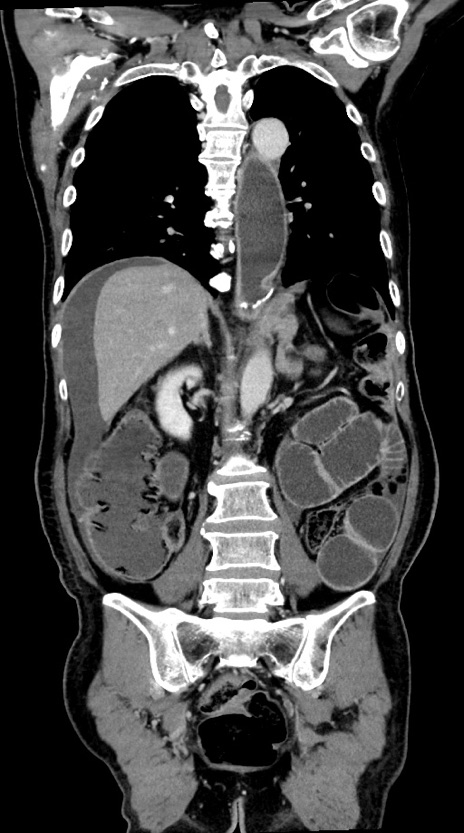

症例28(冠状断像)

【症例】60歳代男性

【主訴】嘔吐

【現病歴】胃癌にて胃全摘後。食思不振が悪化し、夜中に嘔吐することがある。

【既往歴】胃癌、胃全摘、脾摘、胆摘後

【データ】WBC 5900、CRP 10.56